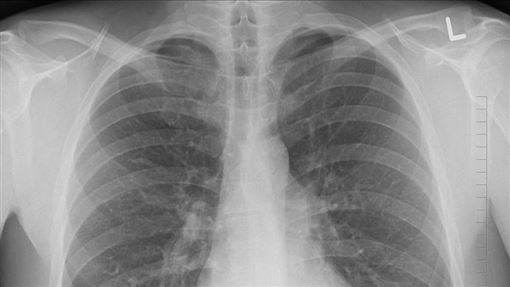

昔日以電影《好小子》爆紅的藝人顏正國7日被爆因病離世,據了解是因患肺腺癌,殯葬業者鋼鐵爸發出訃聞透露,他於下午4點57分離開人世。顏正國的生日正逢雙十節,原本即將迎來51歲生日時,卻在生日前兩天驟然離世,消息令人不勝唏噓。他的最後一篇貼文停留在9月17日,當時分享前往中國旅遊的照片,可見他臉頰凹陷、臉色蠟黃,健康狀況令人憂心。